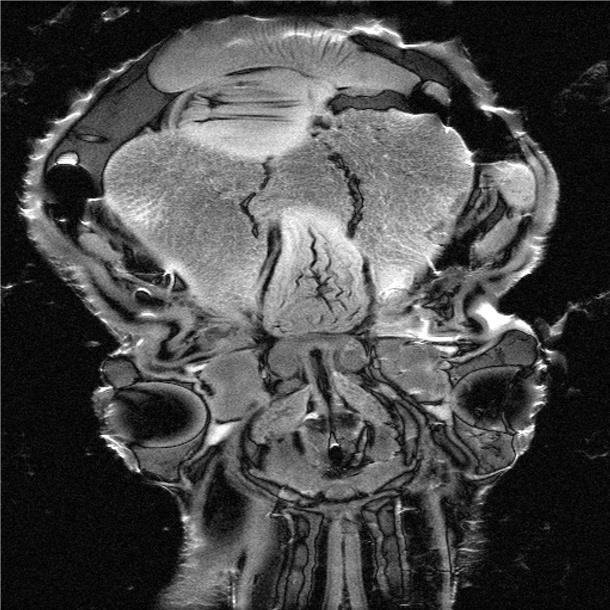

MR-Aufnahme des Köpers und Kopfes eines Octopusses.

MR-Aufnahme des Köpers und Kopfes eines Octopusses. Foto: (C) Integrative Ökophysiologie, Alfred-Wegener-Institut